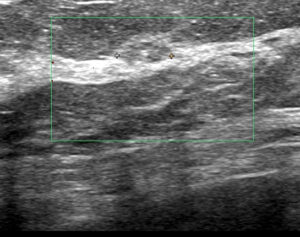

このような、癌を疑うわけでもないので

他院なら経過観察するような症例もCELEROしていると

これは「粘液癌」でした。